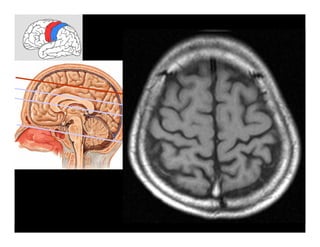

Hình cắt ngang

Hình tái tạo 2D

Hình tái tạo 3D

Thực hiện trên máy MSCT-Chợ rẫy